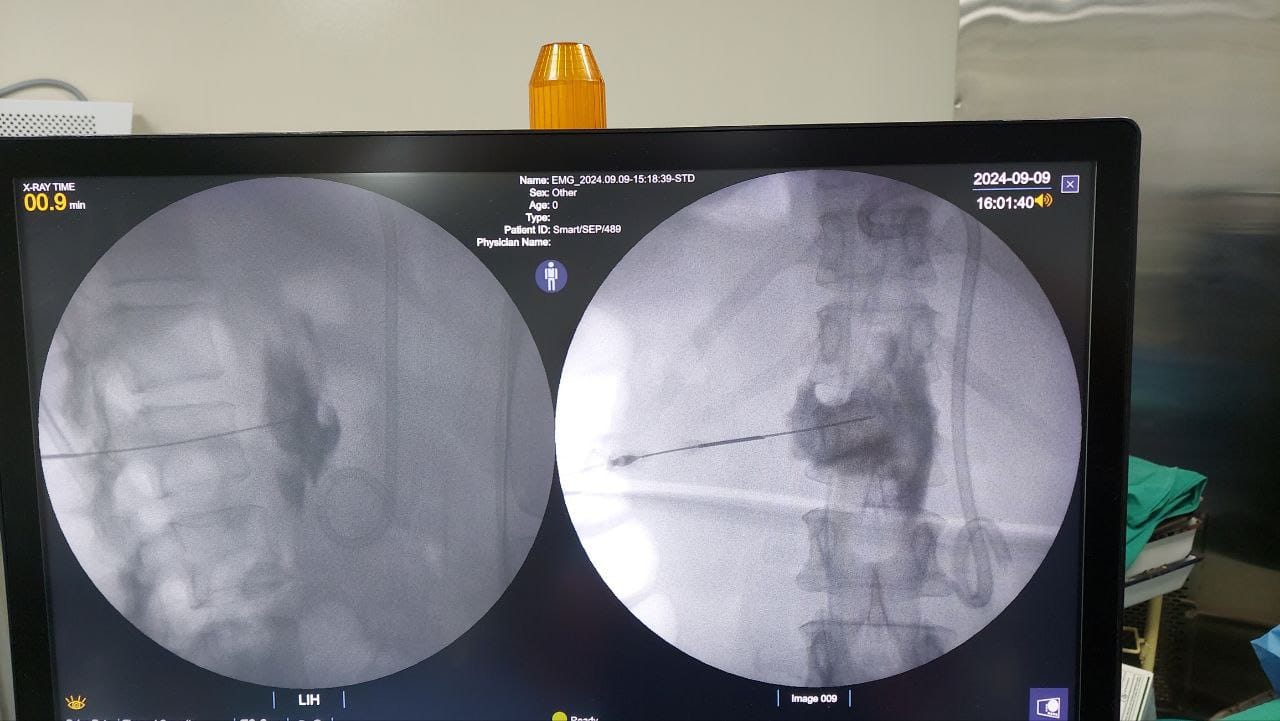

Struggling with chronic pain? Get advanced, personalised pain management from Dr. Manish De, one of Kolkata’s leading pain specialists. From knee pain, heel pain, low back pain, frozen shoulder, migraines, cancer pain to post-TKR persistent pain—Dr. De offers safe, evidence-based treatments across multiple locations: